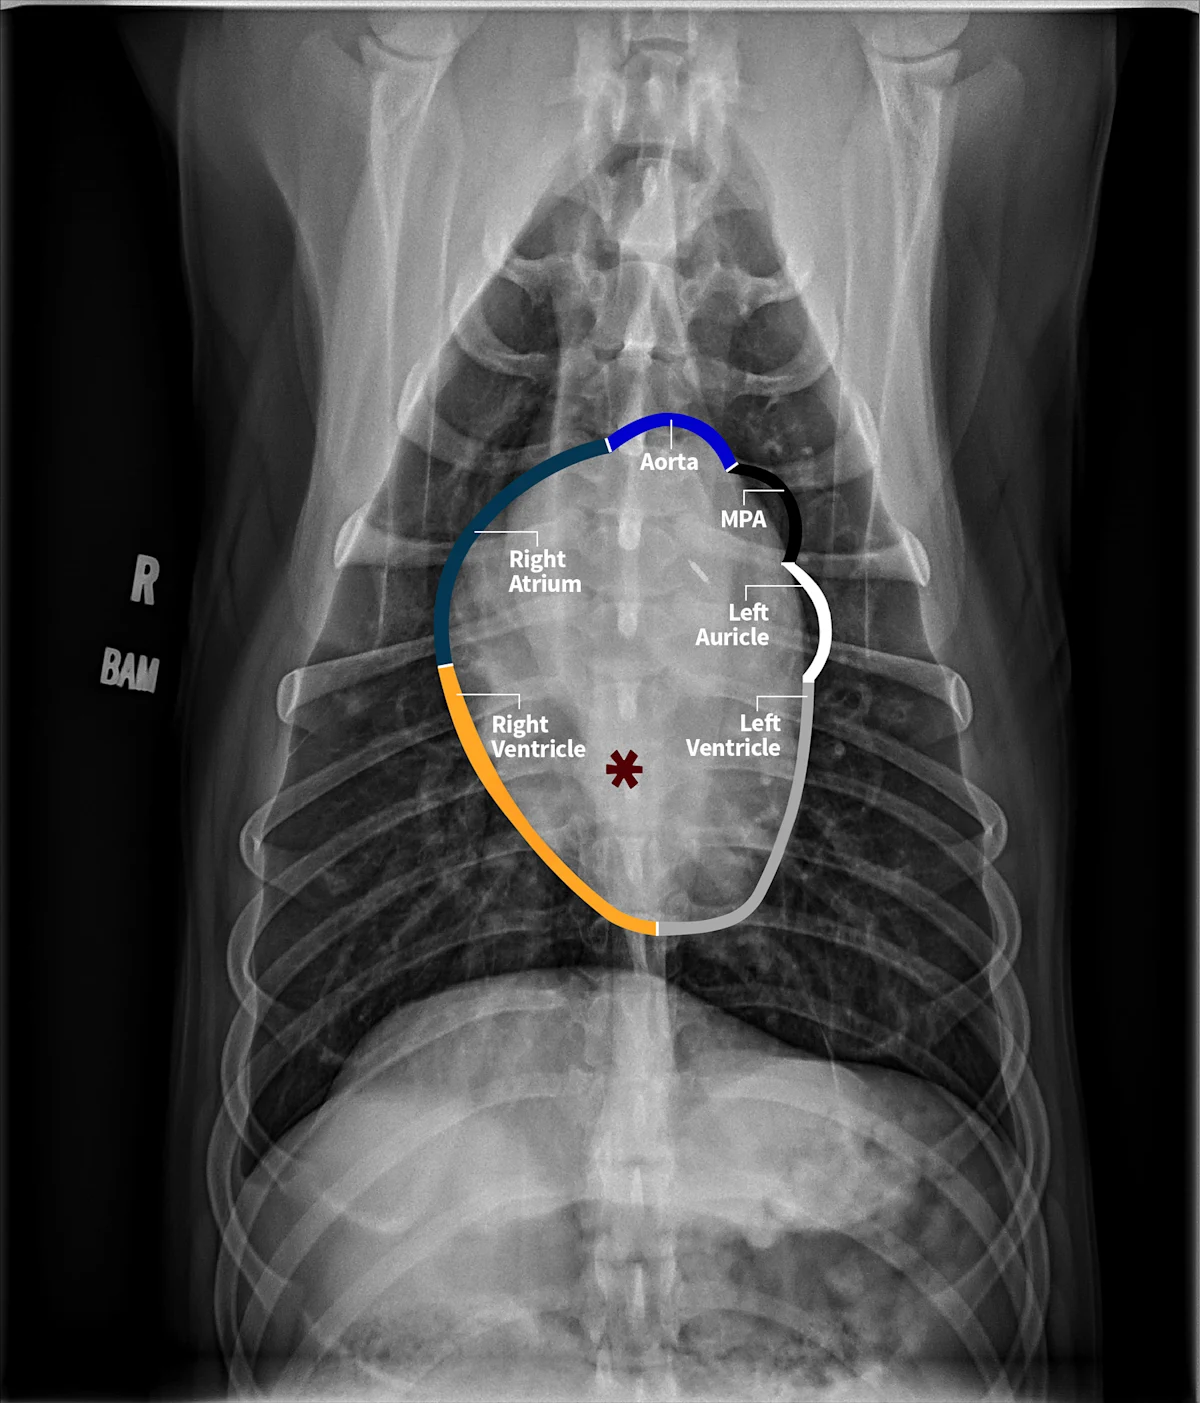

The cardiac silhouette should be evaluated systematically. Using the clockface analogy when evaluating DV or VD projections, the apex of the heart is located at ≈5 o’clock, and the right ventricle is in the region between 5 and 6 o’clock to 9 o’clock, followed by the right atrium, aortic arch, main pulmonary artery (MPA), left auricle, and left ventricle (Figure 4). A similar approach can be followed when evaluating the heart in a lateral projection. The terms cranial and caudal waist or borders are used to describe regions of the cardiac silhouette (Figure 5). Changes within particular regions can indicate which structure is likely abnormal and highlight potential underlying disease processes.

FIGURE 4 Normal VD projection in a large-breed dog showing regions of the cardiac chambers. Orange, navy blue, royal blue, black, white, and gray borders indicate region locations of the right ventricle, right atrium, ascending aorta, MPA, left auricle, and left ventricle, respectively. Abnormalities of the great vessels or auricles would result in focal bulges in their respective regions (not present in this image). The left atrial body (asterisk) can be seen. Illustration courtesy of Jose Narvaez Perez